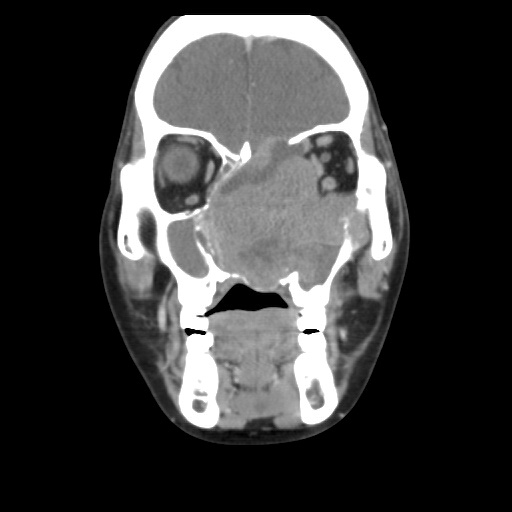

「鼻竇癌是比較少見的一種頭頸癌,在頭頸癌之中比率不到百分之五。」板太太的主治醫師耳鼻喉科陳培榕副院長表示,病理切片檢查結果發現,這是組織細胞型態較罕見的神經內分泌癌,腫瘤大小約七*八*六公分,不僅位置非常深且涵蓋範圍很大,包括腦部顱底、腦膜、雙側鼻腔、左上頜竇及左眼窩內側等重要部位,且顱底的腫瘤有持續向上生長近入顱內壓迫腦部的狀況,外觀也因腫瘤將眼睛和鼻子擠壓變形。

*左圖於2019/12/18攝

經過陳培榕副院長與血液腫瘤科王佐輔主任討論後,決定先進行引導式化療,先把腫瘤縮小,進而能達到開刀及輔助性的放射治療。陳培榕副院長表示,板太太在第一次引導式化療後,腫瘤明顯小了很多,讓醫療團隊更有信心。歷經一個半月、三次的引導式化療,幸好,並沒有出現嚴重的化療副作用,起先腫瘤壓迫顱底、鼻腔和眼睛的狀況,在化療後都獲得控制,甚至明顯縮小至約五公分。